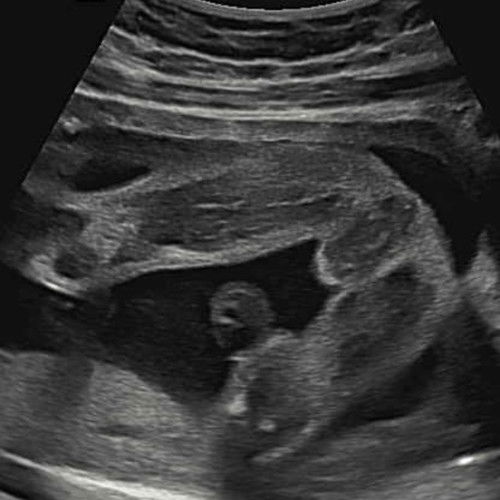

น้องเป็นผู้หญิงรึเปล่าคะเเม่ๆ

ขอความคิดเห็นจากแม่ๆหน่อยค่ะว่าน้องน่าจะเป็นผู้ชายหรือผู้หญิงคะ ดูไม่ออกเลยค่ะ

#ขอบคุณสำหรับคำตอบค่ะ #ท้องแรกคะ